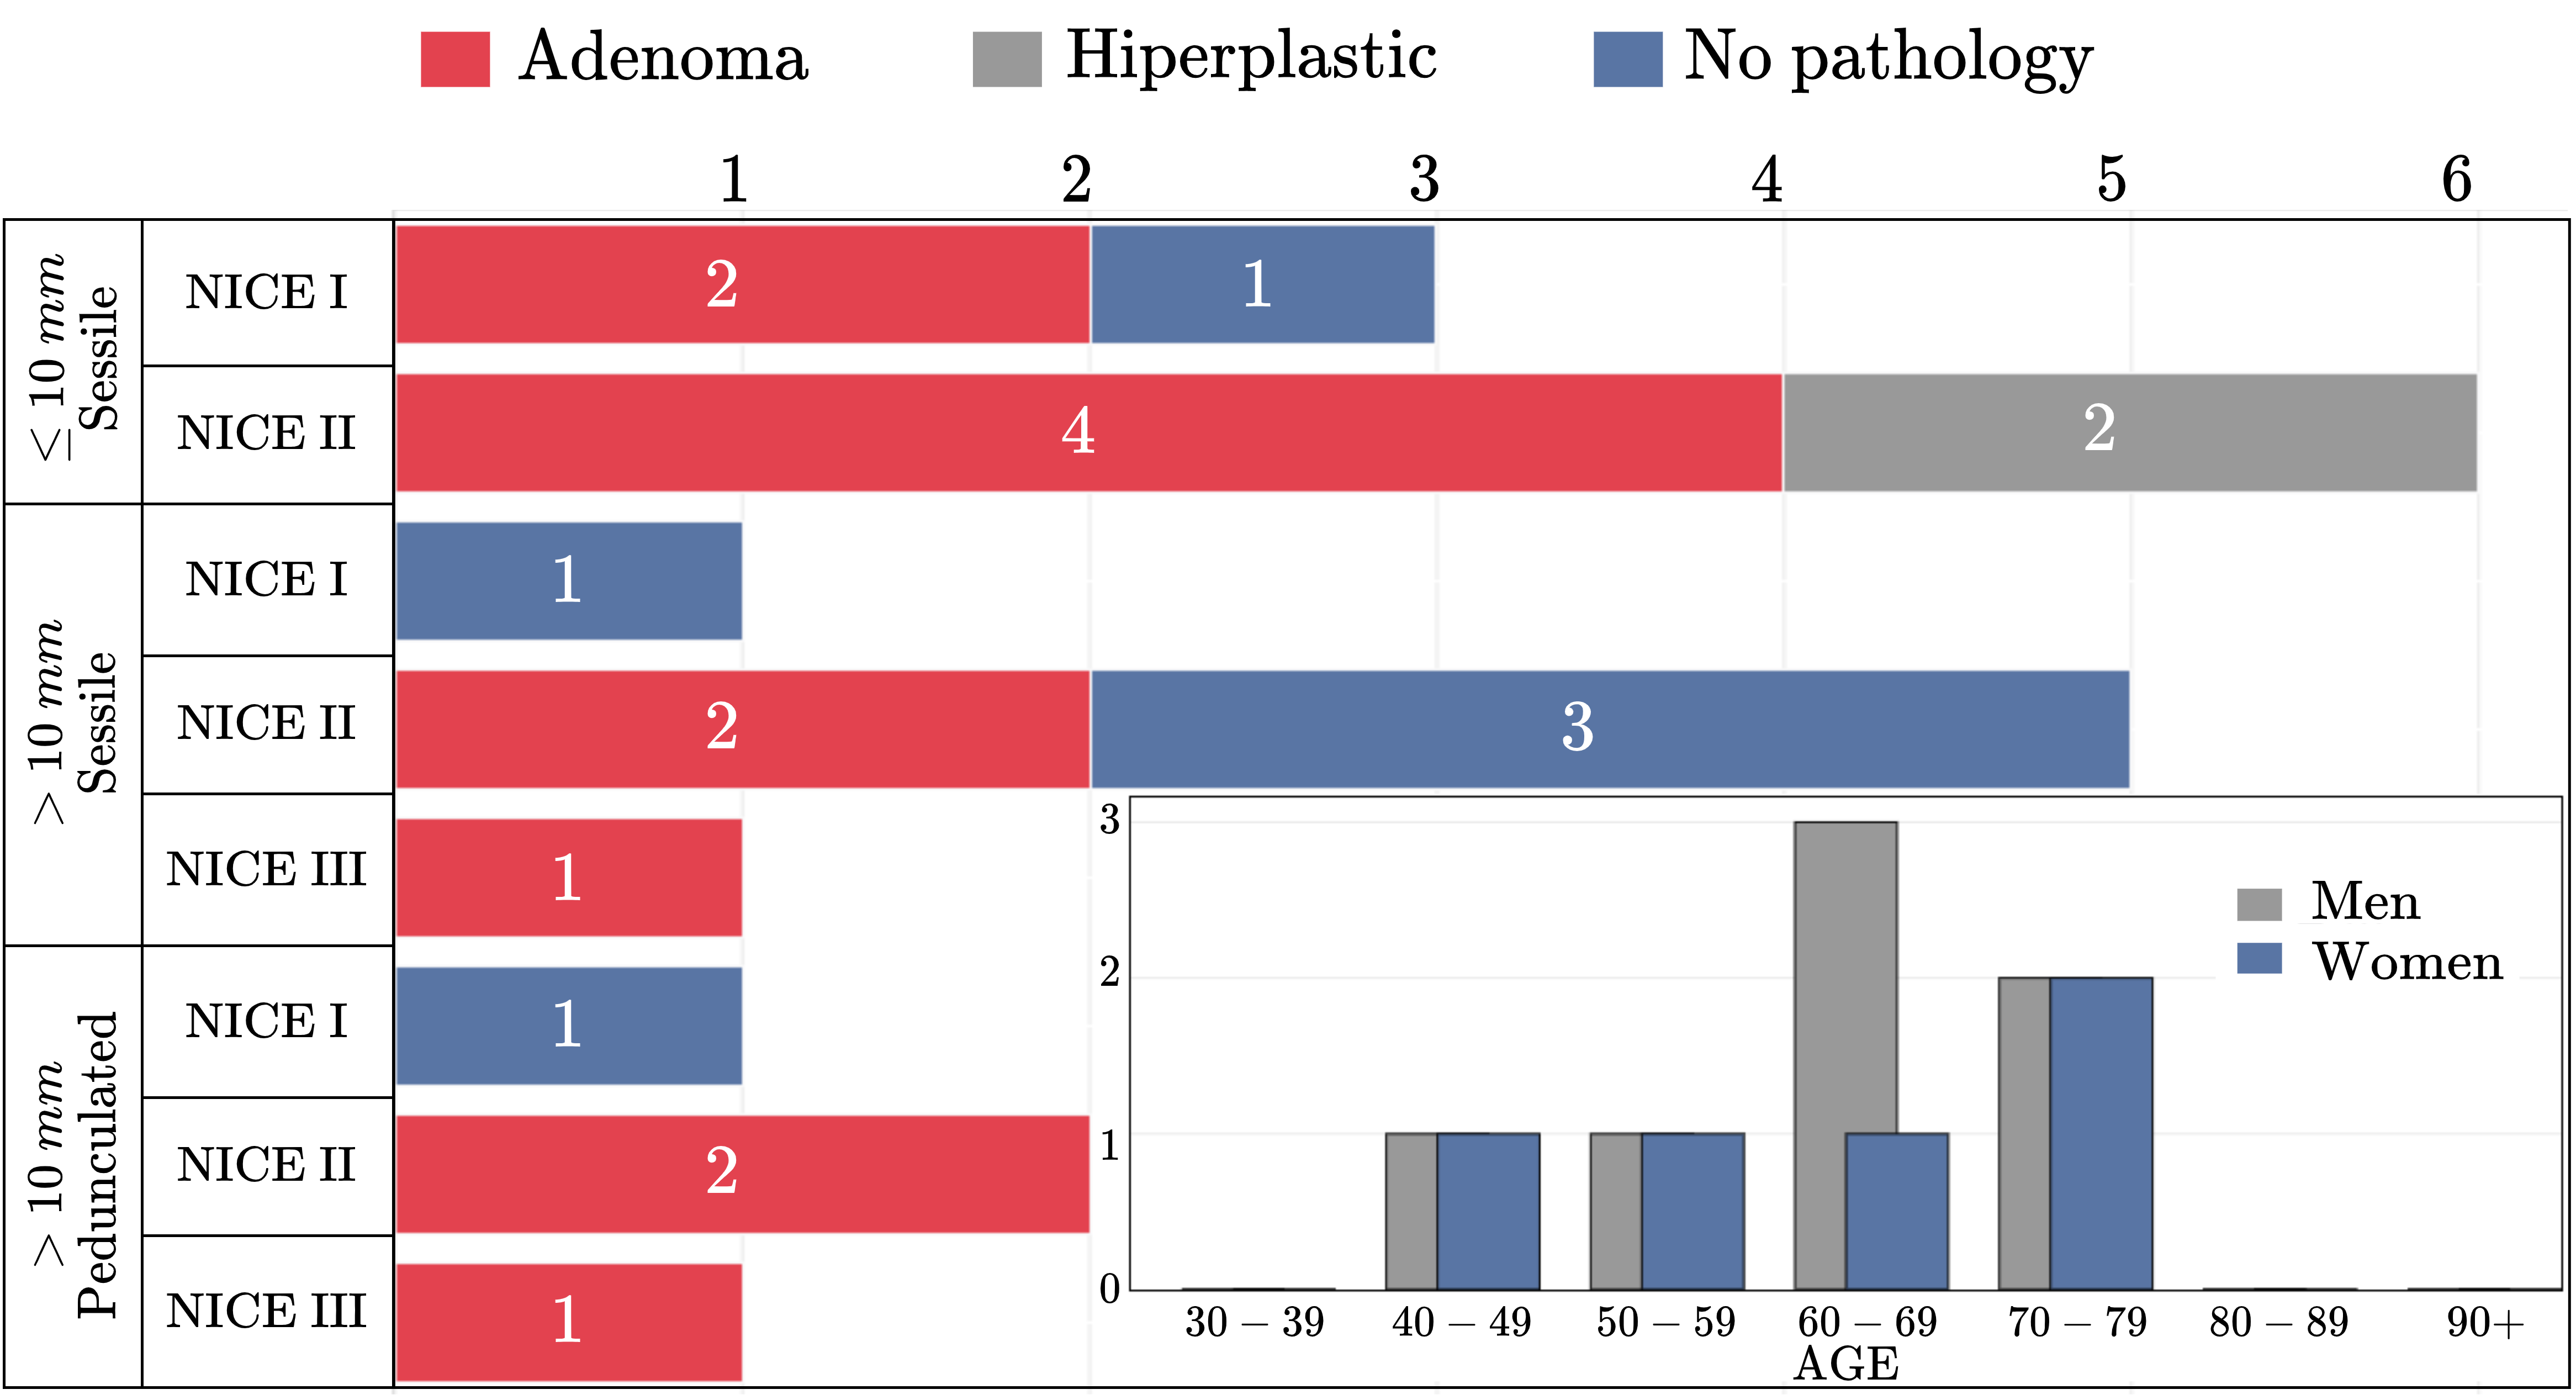

Figure 2 illustrates data distribution of COLON dataset based on demographic variables such as age and gender. As observed, the majority of patients are older than 50 years, with a gender distribution, except for the interval of 60-69 years (two additional samples for men). The dataset was also analyzed in terms of polyp malignancy, following the NICE protocol, and also regarding the histopathological classification: adenoma, hyperplastic, and non-pathological cases. This analysis is valuable for quantifying the capabilities of strategies to correlate detection with malignancy and stratifying polyps. Furthermore, the COLON dataset has been categorized and quantified based on polyp size, a main macroscopic feature associated with malignancy. It should be noted that many of the recorded sequences have polyps smaller than 10 mm, which results in a challenge for strategies, but with major value in supporting detection efforts.